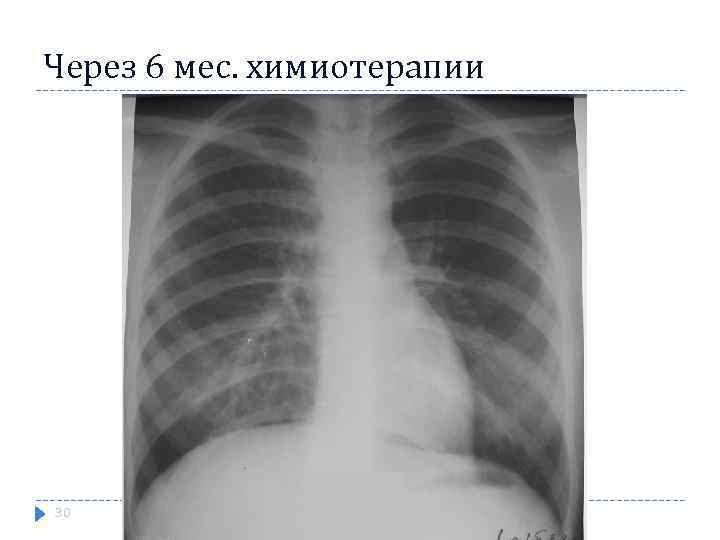

Через 6 мес. химиотерапии 30

Через 6 мес. химиотерапии 30